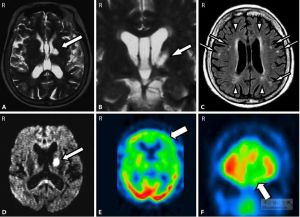

漫畫配圖